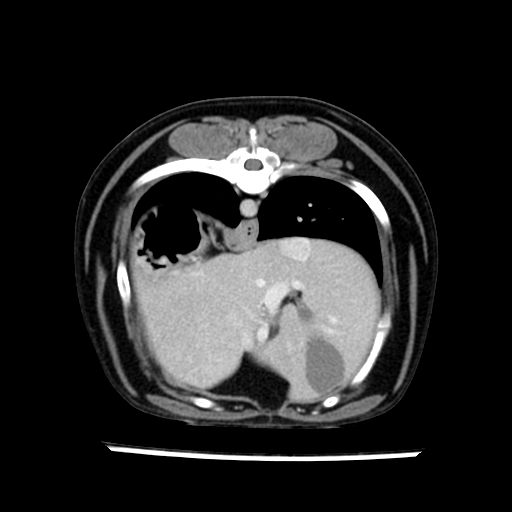

prescritto esame TAC

sequenza immagini limitata al fegato reni e surreni

le immagini ecografiche rispetto alla tac datano circa 7 mesi prima ,le surrenali sono normali nonostante il test acth sia risultato positivo .all’esame TAC dopo diversi mesi risultano aumentate armonicamente nel volume e si individua un forte sospetto di adenoma ipofisario .

sospetto adenoma ipofisario vs. meno probabilmente meningioma della base; intertiziopatia polmonare; lesione espansiva epatica, verosimilmente del lobo laterale sinistro, di sospetta natura neoplastica; lesioni spleniche di natura da definire; iperplasia/ipertrofia delle ghiandole surrenali, bilateralmente; vertebra di transizione del rachide toracico; tenosinovite cronica del muscolo bicipite brachiale di destra.